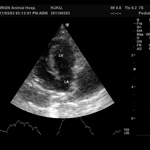

- 심장 초음파 검사

- 고양이 심장 질환의 가장 정확한 진단 방법은 심장 초음파 입니다. 고양이는 개와 달리 심장 이상에 의한 임상증상이 거의 나타나지 않는 경우가 많아, 신체검사, pro-BNP 검사와 더불어 심장 초음파 검사는 반드시 실시해야 합니다.

심장 초음파 검사용 전용 탐촉자와 컬러 도플러를 이용하여 심장 상태를 세밀하게 판단하고 이에 맞춰 내복약 투약 및 식이/환경 관리에 대한 정보를 제공하고 있습니다.